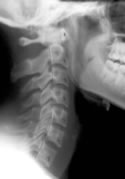

Chiropractic Improves Cervical Spine Lordosis

Cervical spine curve and chiropracticThe latest scientific research on whiplash injuries shows that automobile collisions can cause ligament damage to the cervical and lumbar spine. Numerous studies have shown that zygapophysial facet joints can be stretched during a rear end collision, and recent studies have shown injury to the anterior longitudinal ligament and the transverse ligament.

Identifying these ligamentous injuries, however, can be difficult. The ligaments themselves may be detected on MRI, but they cannot be seen on normal radiographs. It is more likely that the ligament injury will result in changes to the alignment of the cervical spine, and that can be detected with plain films.

A 2002 study1 compared the angle of cervical lordosis between whiplash patients and healthy controls. They found a statistically significant difference between the two groups, suggesting that whiplash injuries may indeed alter cervical spine alignment.

Now, a new study2 has shown that chiropractic treatment can improve cervical lordosis in patients after a motor vehicle collision.

The authors of this current study began with 13 patients who had been in a car crash. They obtained a neutral cervical radiograph taken in the natural standing position. Then, each patient was treated by a chiropractor. The patients had an average age of 24, and the average number of chiropractic adjustments was 17.7.

After a period of care, neutral radiographs were again taken, and both the pre- and post-treatment films were evaluated by a second chiropractor who was blinded to which films belonged to which patient.

The cervical curve was measured in each of the x-rays.

The authors found the following:

10 of the 13 patients showed an increase in the cervical lordosis found on x-ray. The average increase found in the patients was 6.4°.

One patient showed no change and two patients showed a decrease in cervical lordosis.

This study suggests that chiropractic adjustments do indeed increase cervical lordosis, which may be helpful for patients suffering from auto injuries. The sample size in this study was small, and the authors stress the need for further study into this matter.